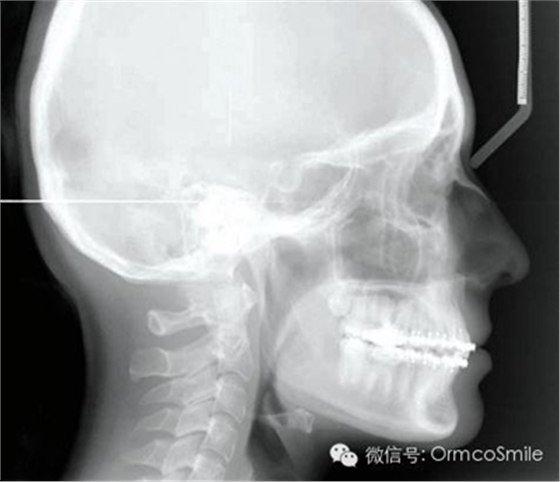

治療目標(biāo)為:遠(yuǎn)中移動(dòng)上頜右側(cè)磨牙,達(dá)到安氏Ⅰ類尖牙、磨牙關(guān)系。治療前,拔除上頜左側(cè)第三磨牙,將一直徑2mm,長(zhǎng)14mm的鈦骨釘植入上頜腭中縫,位于切牙孔后4-5mm,中線旁3-4mm。用1.3mm直徑的鉆助攻植入螺紋釘。一周之后,取印模并灌制模型,將螺紋釘?shù)念^部用蠟包圍,從螺紋釘上延伸出連接第一前磨牙的0.8mm的鋼絲??趦?nèi)試戴后,用光固化樹脂將從螺紋釘上延伸出的弓絲與上頜第一前磨牙粘接在一起,0.016*0.022英寸不銹鋼絲片段弓加鎳鈦推簧置于上頜第一磨牙和第一前磨牙間,每側(cè)250g力推動(dòng)上頜磨牙向遠(yuǎn)中,磨牙到位后拍攝頭側(cè)位片。

經(jīng)測(cè)量,上頜第一磨牙遠(yuǎn)中移動(dòng)3.5mm,達(dá)到磨牙Ⅰ類關(guān)系,同時(shí)壓低2mm,而第一前磨牙和上頜切牙沒有明顯的移動(dòng)。上頜第一前磨牙有3°的輕度前傾,這可能是由于上頜只植入了1顆螺紋釘?shù)脑颍髡叻治霾捎脙深w螺紋釘可以減少這種副作用。在上頜磨牙遠(yuǎn)中移動(dòng)過程中,下頜平面角減少了1°,且其持續(xù)到正畸治療結(jié)束。上頜牙弓寬度有輕度擴(kuò)大。